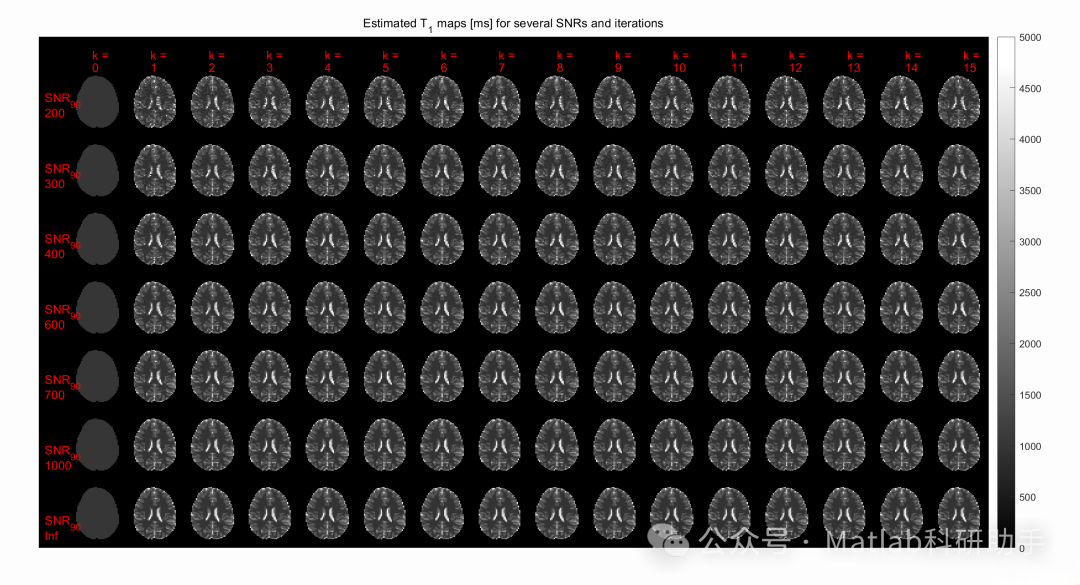

⛳️ 运行结果